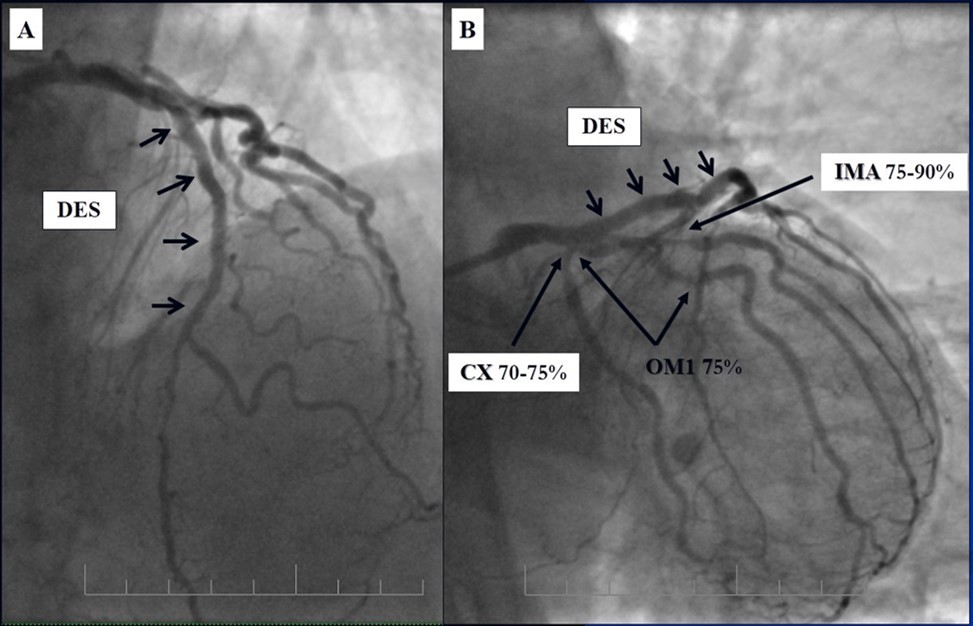

In the first stage, despite the fact that BMS is contraindicated in diabetic patients, RCA was stented with 3 bare-metal stents (BMS) (Rebel, Boston Scientific) (due to financial problems - drug-eluting stents was not covered by insurance). We used BMS to have at least temporarily patent RCA during LMCA stenting (Figure 5) (we believe that, when RCA is functional, LMCA stenting is safer). LAD was stented with 2 drug-eluting stents (Resolute Integrity, Medtronic). After the first PCI patient’s symptoms were relieved (Figure 6).

Figure 5.A, B, C - Stenting of the RCA with BMS; D - Angiography result.

A, B, C - Stenting of the RCA with BMS; D - Angiography result.

Figure 6.A, B - Stenting of the LAD with DES; C - Angiography result.

A, B - Stenting of the LAD with DES; C - Angiography result.